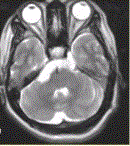

问题 患者女,41岁。右侧面肌抽搐。MRI显示如下图。 关于MRI,描述正确的是

选项 A.右侧桥前池可见T1WI等信号及T2WI高信号 B.未见异常 C.右侧三叉神经未见异常 D.右侧三叉神经可见包绕 E.基底动脉未见异常 F.基底动脉可见包绕

答案 ADF